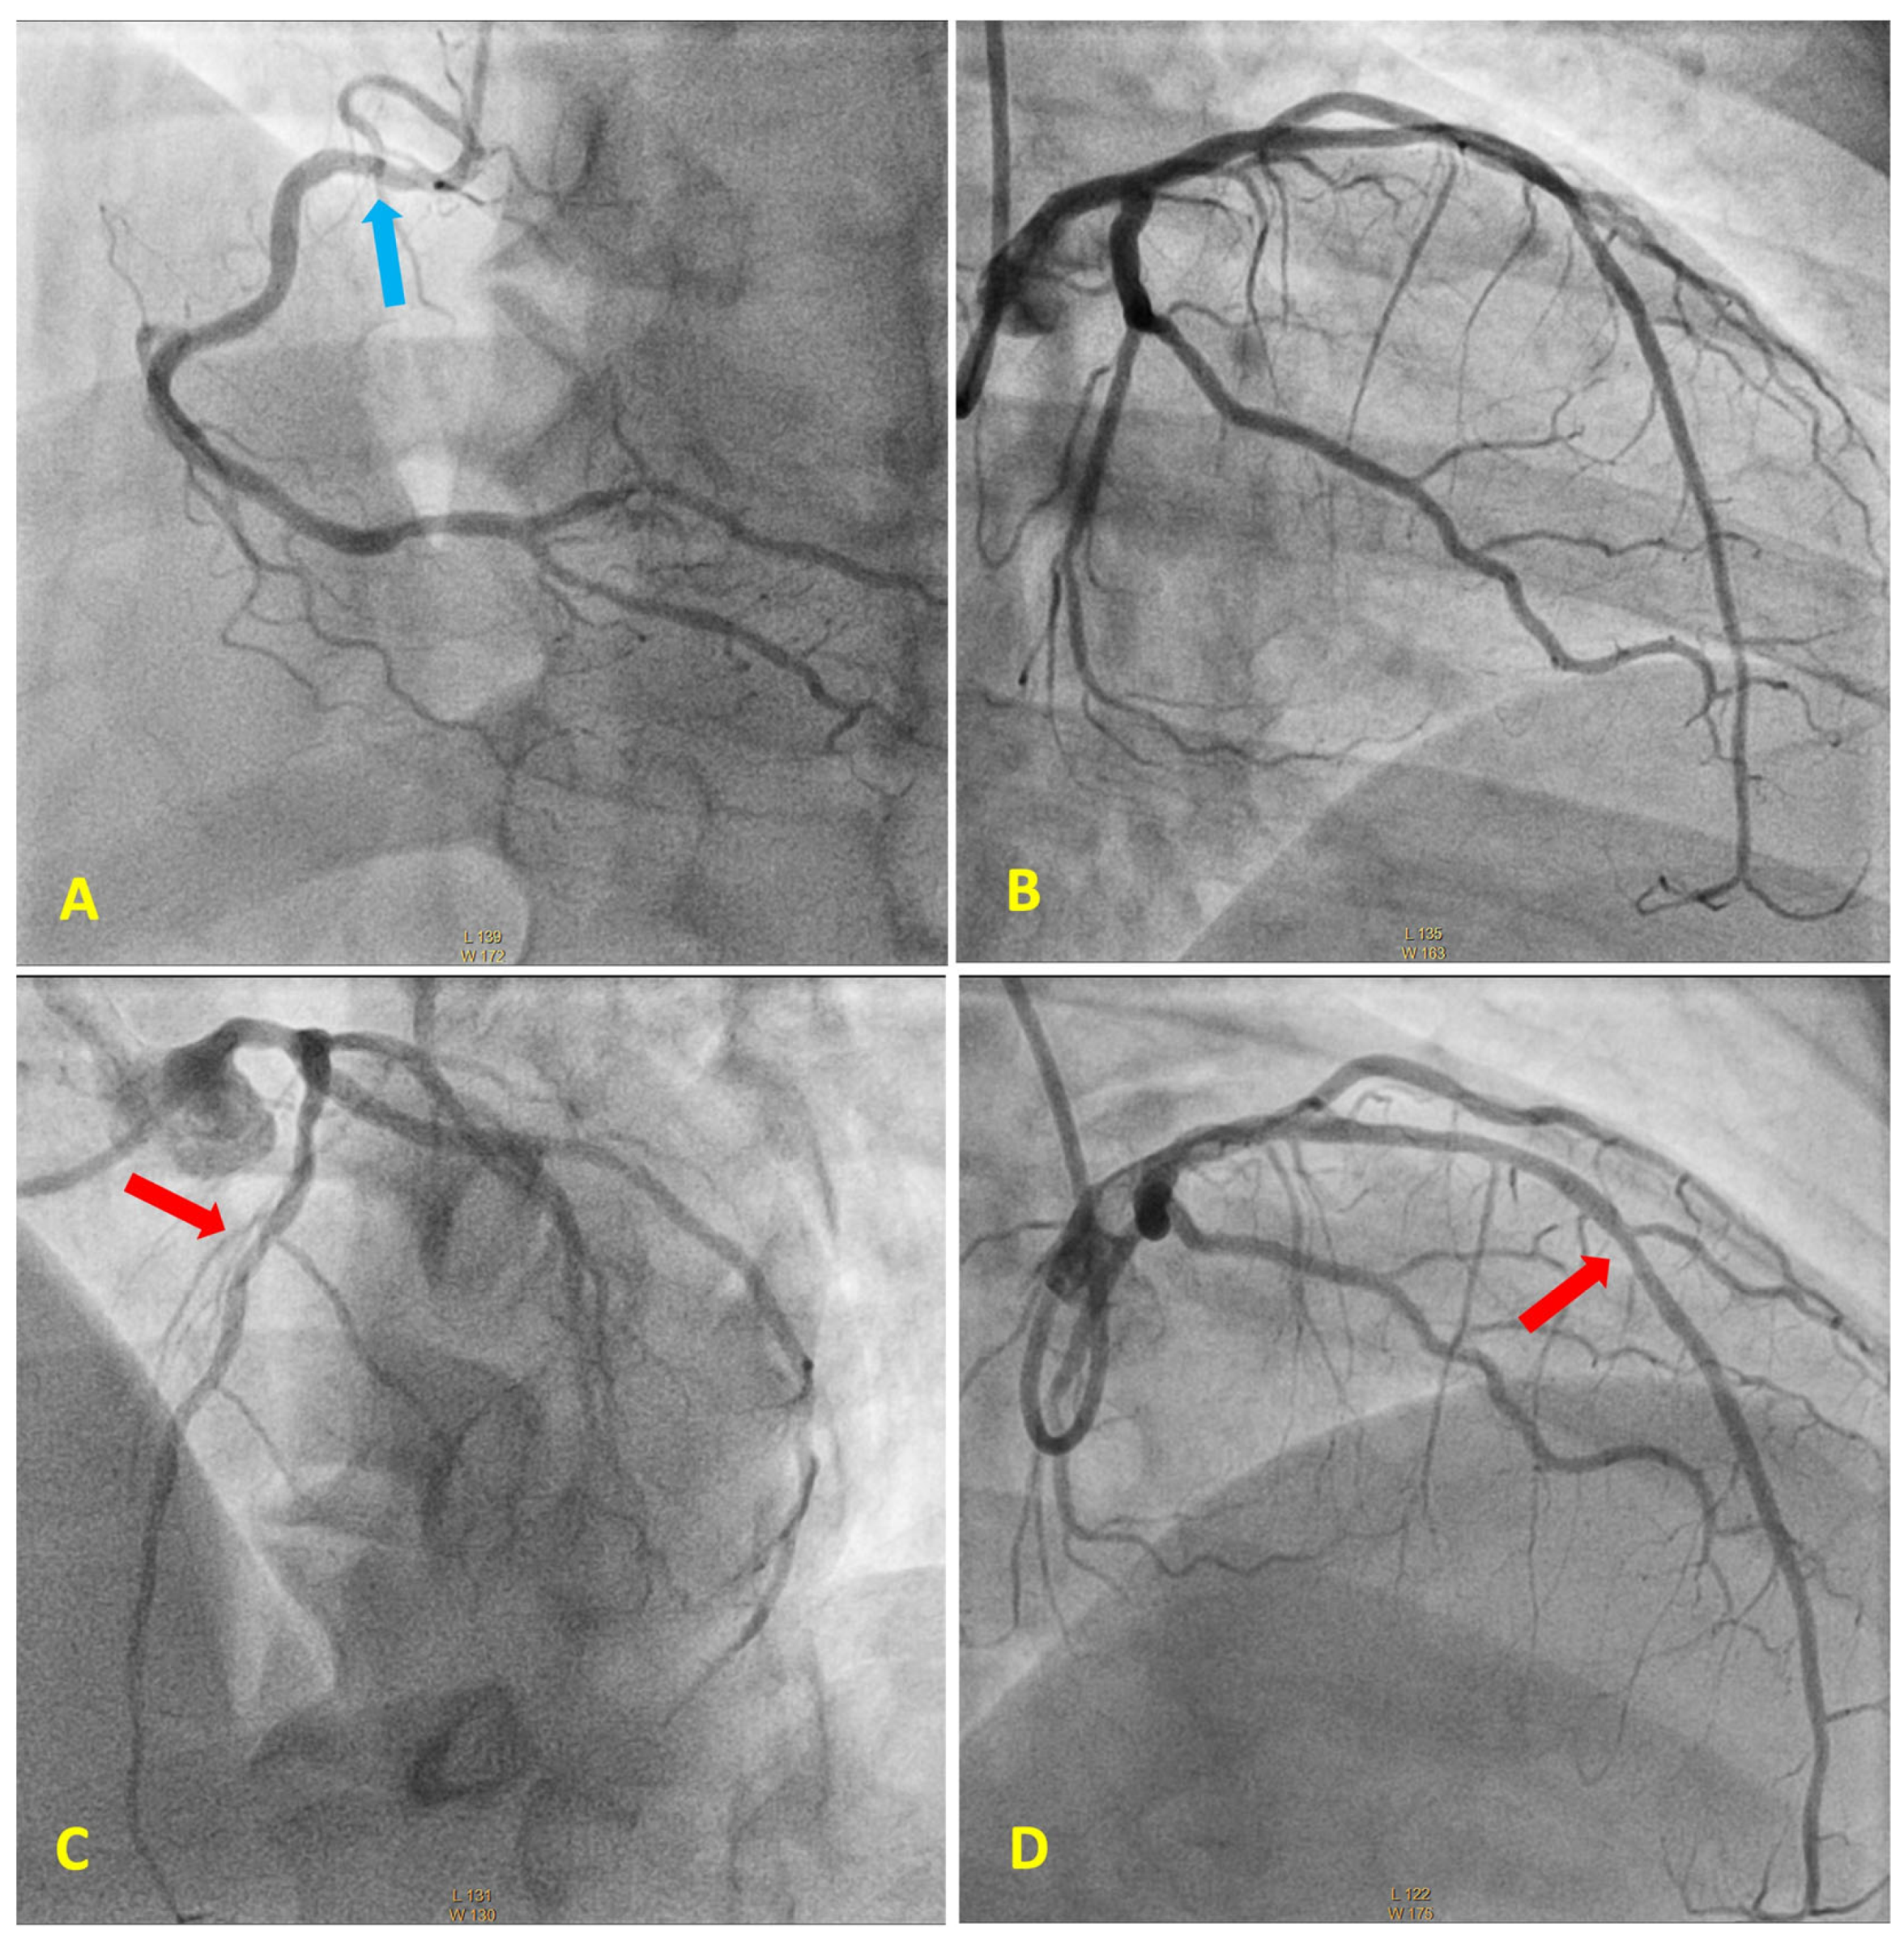

Acute Coronary Syndrome with Non-Obstructive Plaque on Angiography and Features of Vulnerable Plaque on Intracoronary Optical Coherence Tomography

3. Case Report